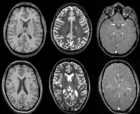

• RegLib C19 thumb all.png Case 19: Multi-contrast group analysis: intra- and inter-subject registration of multi-contrast MRI